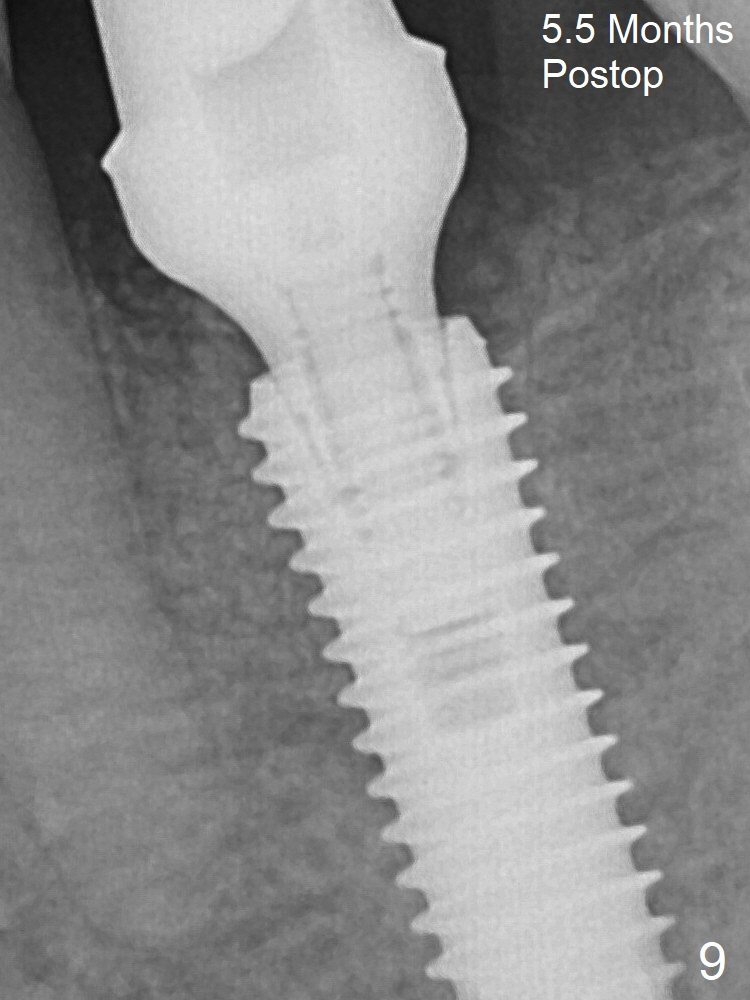

Due to severe buccal plate resorption, a shorter implant is placed (Fig.6; 5x15 mm in stead of 18 mm). There is at least 2 mm gap buccally for Vanilla Graft, which is also placed next to the implant and the neighboring root (Fig.7 double * ). Abutment: 6.5x4(4) mm. The distal (D) socket is packed with Collagen Plug before bone graft coronally (single *). Both the mesial and distal sockets heal 5.5 months postop (Fig.9), although the apical portion of the distal socket was not filled with allograft (Fig.7 D). The implant was placed mesial. The abutment may be changed to 5.5x5(3) mm or 4.5x15 degrees 3 mm cuff before impression. Next case, osteotomy should be established in the middle of the socket by using Lindamann bur amply.

Bone Shorter Than Expected Last Next Xin Wei, DDS, PhD, MS 1st edition 12/07/2017, last revision 09/02/2018